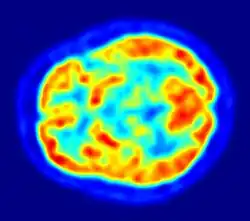

Neuropsychology

Paedophiles show pathological personality traits such as anxiousness, inhibited personality, lack of assertiveness and impaired neuro-cognitive functioning (Black, 2000; Cohen et al., 2002). Dennison, Stough, and Birgden (2001) found paedophiles had significantly higher neuroticism and significantly lower extraversion and conscientiousness when compared to non paedophiles. Paedophiles assessed with neuropsychological batteries (e.g., the Halstead-Reitan and Luria-Nebraska Batteries) show greater impairments largely in verbal and visual-spatial abilities than other nonsexual offenders, or those who commit sexual crimes against adults (Langevin, Wortzman, Wright, & Handy, 1989).

When paedophiles are compared with non criminal community control groups or with men convicted of non sexual crimes, convicted paedophiles typically score lower in intelligence and also have lower immediate and delayed memory performance (Blanchard et al., 2007). Cognitive deficits in paedophiles can be seen to be mediated by the prefrontal cortex, which may account for their behavioural disinhibition, disinhibition of automatic motor responses, working memory deficits, and impairment of cognitive flexibility (Joyal, Black, & Dassylva, 2007).